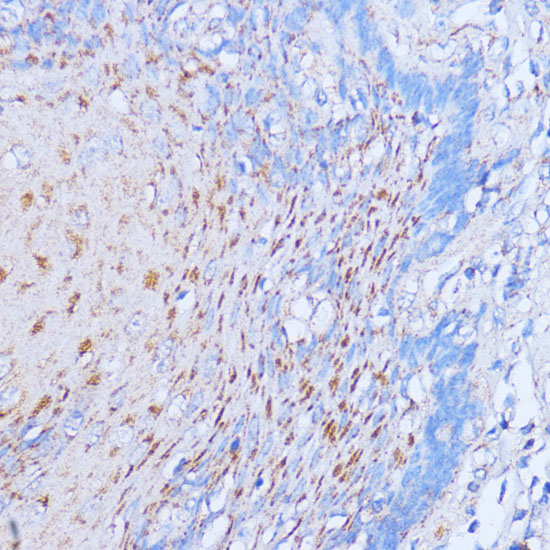

Immunohistochemistry of paraffin-embedded rat pancreas using NME6 at dilution of 1:100 (40x lens).

,

Immunohistochemistry of paraffin-embedded human esophageal using NME6 at dilution of 1:100 (40x lens).

Immunohistochemistry of paraffin-embedded mouse kidney using NME6 at dilution of 1:100 (40x lens).